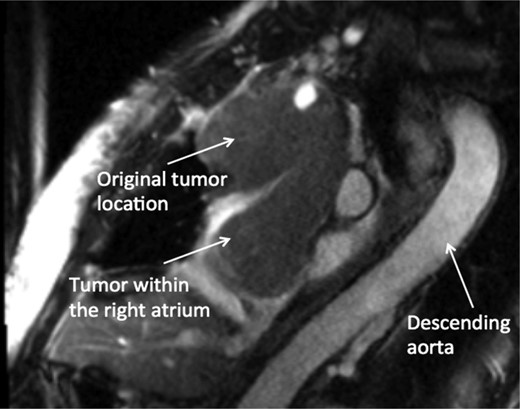

A 74-year-old female presented with facial and upper extremity swelling over the last month. The swelling was worse in the morning and improved throughout the day. The patent also reported dyspnea on exertion. A review of systems was otherwise negative. Social history was notable for 40-pack-year smoking history, but she quit smoking 12 years ago. Her vital sign were stable. Physical examination revealed mild facial swelling, non-pitting edema of the upper extremities and distention of superficial veins of the anterior chest wall and jugular veins. There were no significant laboratory abnormalities. An echocardiogram showed moderate right atrial dilation with a mobile mass in the atrial cavity prolapsing through the tricuspid valve, bowing of atrial septum from right to left consistent with increased right atrial pressure, moderate tricuspid regurgitation and normal left ventricular ejection fraction with no regional wall motion abnormalities. Cardiovascular magnetic resonance imaging revealed a 9.9 × 4.3 cm heterogeneous mass admixed with thrombus in the anterior mediastinum compressing the SVC and endovenously extending into the right atrium (Figs 1–3). Anticoagulation with heparin drip was initiated. A computed tomography (CT)-guided biopsy revealed a tan-colored mass with CD5 lymphocyte predominance, inconspicuous epithelial cells positive for P63 expression and cytokeratin AE1/AE3 that was morphologically consistent with thymoma type B1.

CMR sagittal view: large anterior mediastinal mass with extension into the right atrium.